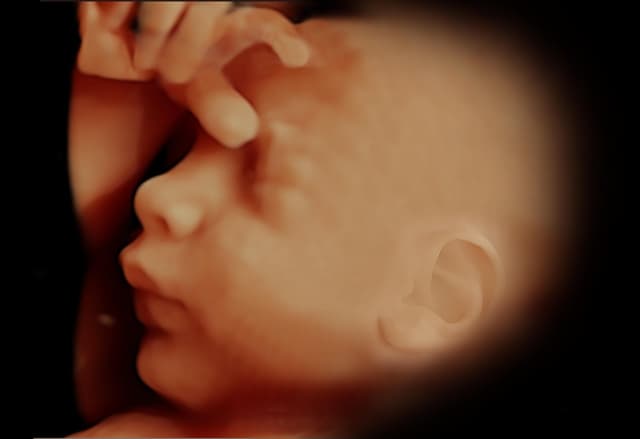

Tecnología avanzada que permite visualizar imágenes en tiempo real y en alta definición del feto, mostrando movimientos y rasgos faciales con gran detalle.